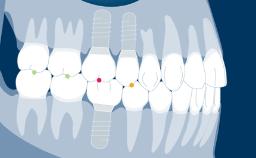

- describe the aspects of denture design that aid in restoring the patient’s overall physiognomy and oral function

- explain the static and dynamic occlusal schemes that contribute to denture stability and chewing efficiency